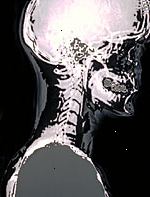

(Skull X-ray studie)

X-paprsky pomocí neviditelné elektromagnetické paprsky energie na výrobu obrazů vnitřních tkání, kostí a orgánů na film. Standardní X-paprsky, jsou prováděny z mnoha důvodů, včetně diagnostiky nádorů nebo kostních poranění.

X-paprsky, jsou vyrobeny s použitím externího záření produkovat obrazy těla, jeho orgánů a dalších vnitřních struktur pro diagnostické účely. X-paprsky procházejí tělesných tkání na speciálně upravené desky (podobně jako fotoaparát filmu) a "negativní" typu obrázek je (pevnější konstrukce je bělejší, že se na filmu).

Když tělo prochází rentgeny, různé části těla, aby různé množství rentgenových paprsků projít. Snímky jsou vyráběny ve stupních světla a tmy, v závislosti na množství rentgenového záření, které pronikají do tkáně. Měkkých tkání v těle (jako je krev, kůži, tuk a sval), aby většina z X-ray projít a se tmavě šedá na filmu. Kosti nebo nádor, který je hustší než měkkých tkání, umožňuje několik rentgenů projít a objeví bílé na X-ray. Při přerušení v kosti, X-ray paprsek prochází rozbité oblasti a jeví se jako tmavé čáry na bílé kosti.

Zatímco X-paprsky lebky se nepoužívají tak často, jako v minulosti, v důsledku použití nových technologií, jako je počítačová tomografie (CT) a magnetickou rezonancí (MRI), zůstávají cenné pro hodnocení kosti lebky zlomenin a odhalování dalších onemocnění lebky a mozku.